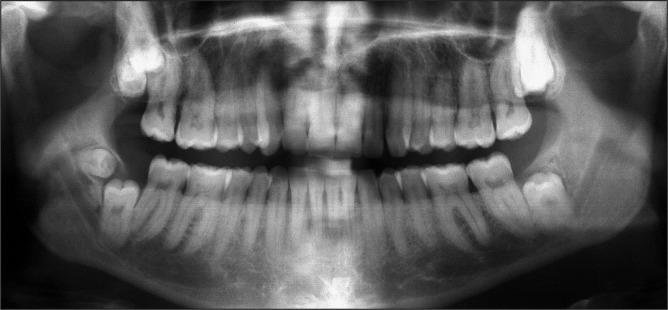

Material and methods: The panoramic radiographs of 179 patients were analysed for supernumerary molars and dysplastic wisdom teeth with special reference to facial tumour type. The results were compared to radiographic findings obtained in panoramic radiographs of age- and sex-matched controls.

Results: The total number of dysplastic or supernumerary molars was 21 (17 individuals, 4.75%) and predominantly a finding of the maxilla (maxilla: 15, mandible: 1, maxilla and mandible: 1). Differences of dental findings between neurofibromatosis type 1 (NF1) patients (n = 15) and the control group (n = 2) were statistically significant (P < 0.01). All individuals with supernumerary molars were diagnosed as being affected with NF1. This difference achieved statistical significance when it was considered that the event may occur at least once per quadrant, and thus the individual potentially needs to be considered four times (P = 0.0038).

Conclusions: This investigation revealed that supernumerary molars and aberrations in wisdom tooth form are more common in patients than in age- and sex-matched controls. There is no association between these findings and a specific feature of the disease, id est facial manifestation of a trigeminal nerve sheath tumour (plexiform neurofibroma). The cause of this phenomenon is unknown. A review of these dental findings on other neurofibromatosis type 1 study groups should be attempted.